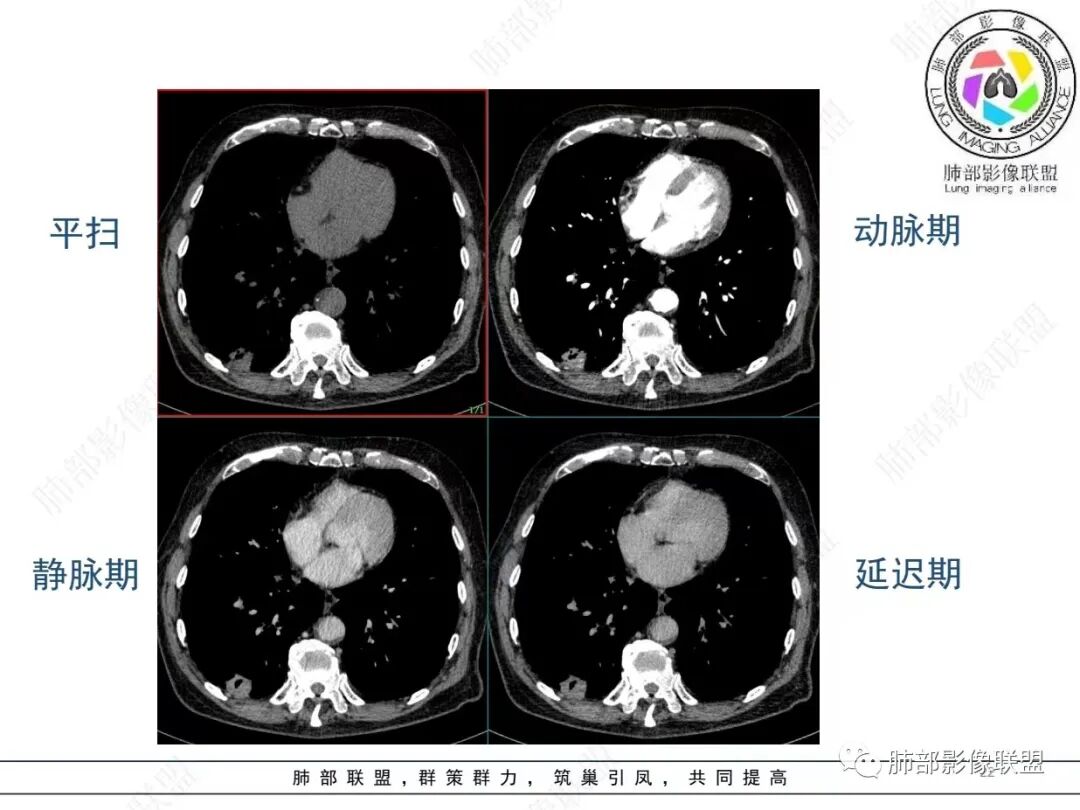

老年男性,发作性气喘,实验室检查白细胞增高。肺部影像表现:右肺胸膜下占位性病变,肺气肿背景,内部可见空腔/空泡影,周围可见小结节,增强动脉期明显强化,静脉期及延迟期强化减低,右侧肺门可见肿大淋巴结,有吸烟史,近年减少,首先考虑恶性肿瘤,肺小细胞癌/鳞癌,隐球菌作为鉴别诊断,病例穿刺活检。

老年男性,气短,胸痛半年,考虑慢性病史,无发热,常见的肺部感染可以排除,右肺下叶基地段靠近胸膜实变影,边缘清楚,不均匀强化,可见空泡征,点状血管影,周围小叶中央型结节,有网格影,支气管扩张,磨玻璃影,肺间质改变,右侧肺门淋巴结肿大,综合考虑恶性肿瘤并肺内转移

老年男性,胸疼入院,影像表现,右肺下叶胸膜下结节,边界清晰,与支气管关系不密切,病灶内见空洞?增强病灶均匀强化,右肺门可见增大淋巴结,考虑恶性病变,小细胞癌,其次鳞癌

老年男性,肺气肿背景,右肺下叶,右肺下叶胸膜处实性结节,形似山丘,有分叶,病灶内可见扩张细支气管/空泡,边缘可见弯曲血管,增强后不均匀强化,可见血管影,病灶胸膜侧呈小波浪??状,局部突入胸膜面,右肺门肿大淋巴结。考虑恶性结节,小细胞肺癌,腺癌,鉴别炎性肉芽肿。建议ct下穿刺活检。

老年男性,肺气肿病史,支气管束增粗,管壁增厚,右肺下叶后基底段胸膜下肿块,土豆征,边界清,有膨隆,小支气管边缘阻断,见集血管束征,肿块强化明显(快进快出特点),并偏心空洞,胸膜下栽赃,周围肺结构破坏(蜂窝状影表现),右肺门淋巴结转移肿大,血管内皮生长因子偏高,肿块与小支气管,血管束关系密切,强化特点,定恶性肺肿瘤,小细胞Ca。

老年男性,肺气肿,右肺下叶胸膜下结节,边缘毛躁,周围多发间质增厚,临近胸膜下脂肪间隙模糊,增强后动脉期不均匀强化,延迟期强化较低,右肺门肿大淋巴结,考虑恶性,鳞癌,小细胞肺癌,鉴别炎性肉芽肿性结节

右肺下叶胸膜下结节,边界清,边缘平直膨隆,血管集束,其内空洞,明显不均匀强化,考虑腺癌?小细胞癌?鉴别隐球菌

肺气肿,胸膜下结节,边界清晰,边缘毛糙,病灶内见空洞,增强病灶均匀强化,右肺门可见增大淋巴结,考虑恶性病变,小细胞癌,其次鳞癌,鉴别隐球

老年男性,肺气肿背景,右肺下叶胸膜下团块影,明显强化,其内空泡征,周边血管聚集,右肺门淋巴结增大,考虑腺癌?

右下叶胸膜下结节,宽基底与胸膜相连,结节与胸膜相交呈钝角〈山丘征〉,内可见充气扩张的支气管,中度强化,结节边缘无毛刺,内见走行自然的血管影,提示破坏力及收缩力差,右肺门可见肿大淋巴结,老年烟民,考虑恶性占位,支持小细胞癌

右肺下叶胸膜下结节,呈山丘状,生长在慢支肺气肿间质纤维化的基础上,边缘相对光滑清晰,右肺门淋巴结肿大,强化呈速升速降,老年男性,吸烟史,考虑小细胞肺癌,鉴别隐球

老年男性,吸烟史40年,肺气肿背景,胸膜下结节,边缘膨隆,增强后结节内有片状坏死区,右肺门及纵隔肿大淋巴结,考虑恶性,鳞癌?小细胞代排

老年患者,右下肺胸膜下结节,有血管聚集、空泡征,强化明显,右肺门见肿大淋巴结。考虑腺癌,鉴别肉芽肿性病变

老年男性,长期抽烟病史,右下肺胸膜下结节,有分叶,胸膜下栽桩,肿块增强可见明显不均匀强化,考虑恶性,鳞癌可能性大,鉴别小细胞肺癌。

恶性明确(右肺门淋巴结明显肿大,中心坏死,坏死边界不清楚,胸膜下馒头样肿块,血管集束,支气管阻塞,动脉期明显强化,内部明确的供血血管提示肿瘤细胞密集,局部坏死边界不清,强化快进快出,邻近胸膜强化呈胸膜尾征,提示胸膜受侵),病理符合周围性低分化鳞癌(老年男性,长期吸烟史,肿块强化明显,快进快出,坏死边界不清楚,阻塞性炎症及阻塞性肺气肿,肺门淋巴结肿大,坏死,邻近支气管壁增厚支持粘膜下侵润生长),白细胞总数高,动脉期强化那么明显,腺癌合并感染倒是要高度警惕。

老年男性,吸烟史+肺气肿背景,右下肺胸膜下肿块(坏死+内部血管影+快进快出),右侧肺门淋巴结肿大,考虑:恶性、鳞?高级别腺待排(总体感觉偏软)。

男,80,发作性气喘半年,加重1天。长年大量吸烟史。肺部CT:肺气肿背景,右肺胸膜下实性占位,处于外周大疱带与气肿带交界,山丘征,边缘膨隆,边界较清,血管集束,周围可见小结节。增强不均匀强化,内可见迂曲模糊血管影,右肺门、隆突下可见肿大淋巴结。首先考虑恶性肿瘤,小?鳞?鉴别PC、TB等。